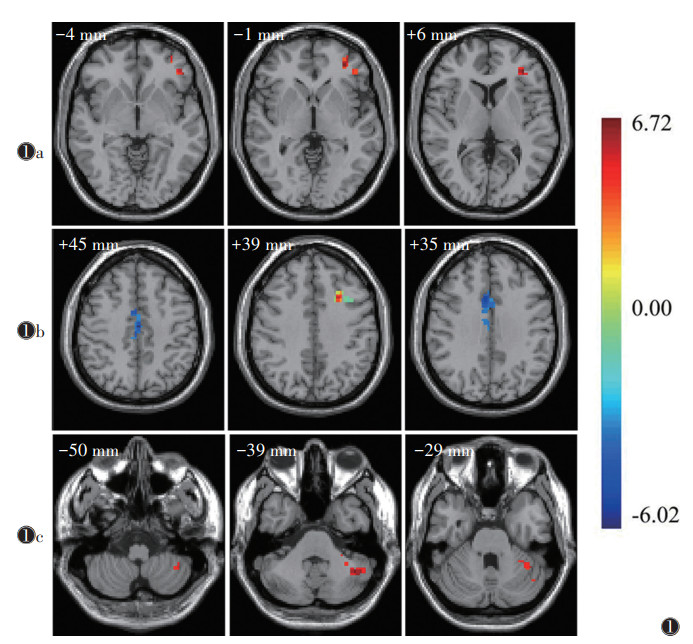

2 结果 2.1 3组ReHo值比较与对照组相比,优势半球脑梗死组左侧三角部额下回的ReHo值显著增高(t=4.97,P < 0.05);非优势半球脑梗死组左侧额中回的ReHo值显著升高(t=6.01,P < 0.05),左侧内侧和旁扣带脑回、右侧枕上回的ReHo值显著降低(t=-6.02,-5.25;均P < 0.05)。与非优势半球脑梗死组相比,优势半球脑梗死组左侧小脑的ReHo值显著升高(t=4.51,P < 0.05)(表 1~3,图 1)。

| 注:图 1a~1c分别为优势半球脑梗死组与对照组、非优势半球脑梗死组与对照组、优势半球脑梗死组与非优势半球脑梗死组的ReHo值比较(体素水平P < 0.01,团块水平P < 0.05,GRF校正)。右边为t值颜色条,冷色代表ReHo值降低,暖色代表ReHo值升高,颜色越红表示ReHo值越高,颜色越蓝表示ReHo值越低,靠近字母侧为大脑右侧,靠近颜色条为大脑左侧 图 1 局部一致性(ReHo)值差异脑区图 |